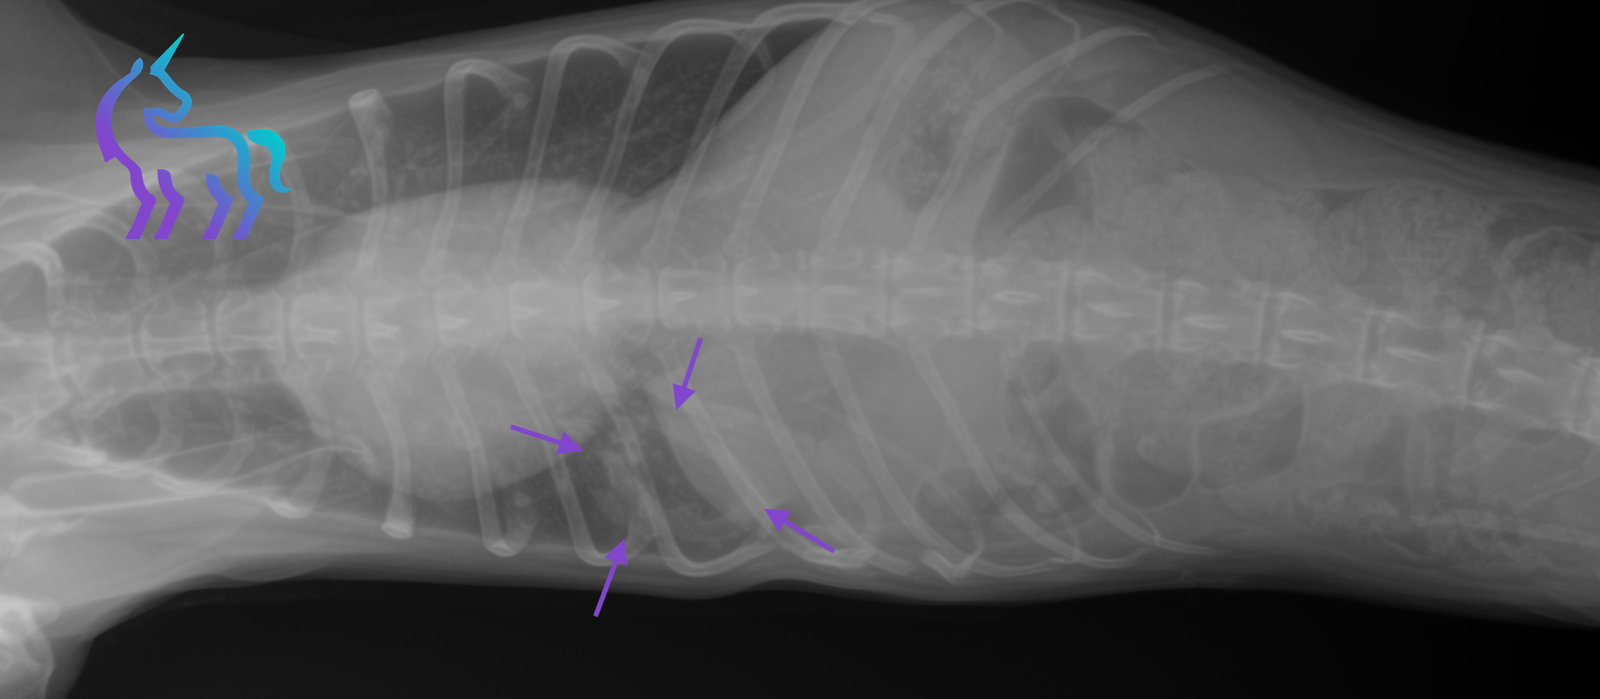

Dissémination métastatique pulmonaire (Aspect miliaire)

Espèce : ChatRadiographies thoraciques montrant de multiples nodules pulmonaires millimétriques diffus, donnant un aspect miliaire sur l’ensemble des lobes.

L’ensemble est compatible avec des métastases pulmonaires, dans un contexte de récidive de tumeur mammaire.

Diagnostic retenu : La radiographie permet ici de poser un diagnostic de dissémination métastatique pulmonaire et de contre-indiquer la chirurgie.